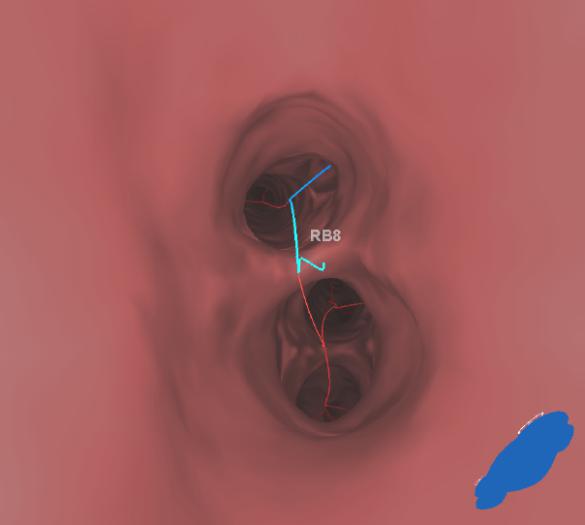

▲术中循着规划路径到达指定部位

置入胸腔镜观察,根据定位病灶位置确定切除范围,确保足够切缘后以胸腔镜切割缝合器行楔形切除,剖开标本见染色位置和病灶完全吻合,术中冰冻提示原位腺癌。